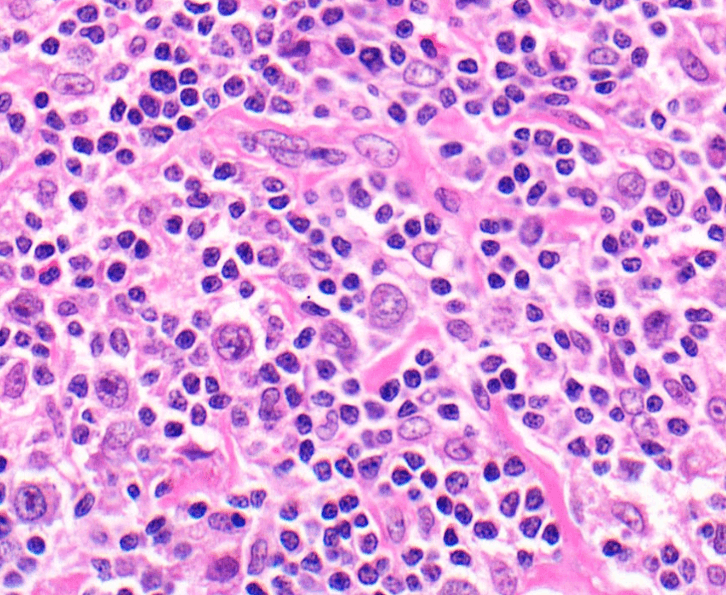

Lymphoma describes the malignancy of lymphocytes, a type of white blood cell which form part of our immune system. There are two main types of lymphoma, Hodgkin’s lymphoma (HL) and non-Hodgkin’s lymphoma (NHL). Approximately 13,900 new cases of NHL are diagnosed in the UK each year, making it the sixth most common cancer in the UK. HL is much rarer, with about 2,100 new cases diagnosed in the UK each year.

Dr Jessica Okosun, a Group Leader in BCI’s Centre for Haemato-Oncology, is currently focusing on a type of NHL called follicular lymphoma. Dr Okosun’s work looks at understanding the molecular processes involved in the initiation of follicular lymphoma, and the genetic diversity that exists in this cancer type. Whilst it is recognised that genetic diversity exists between tumours in different patients with follicular lymphoma, last year a team of researchers led by Dr Okosun found that this diversity also exists between different tumours in the same patient.

Leukaemia describes the malignancy of white blood cells, and is a cancer which starts in blood-forming tissue, usually the bone marrow. There are many different types of leukaemia, and they can be described as acute (those which develop fast) or chronic (those which develop more slowly).